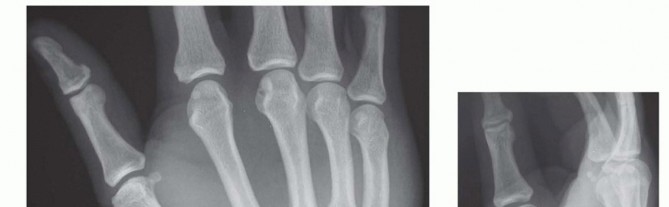

27 MIN READ Dislocations and Chronic Volar Instability of the Thumb Metacarpophalangeal Joint يناير 2023 Read More